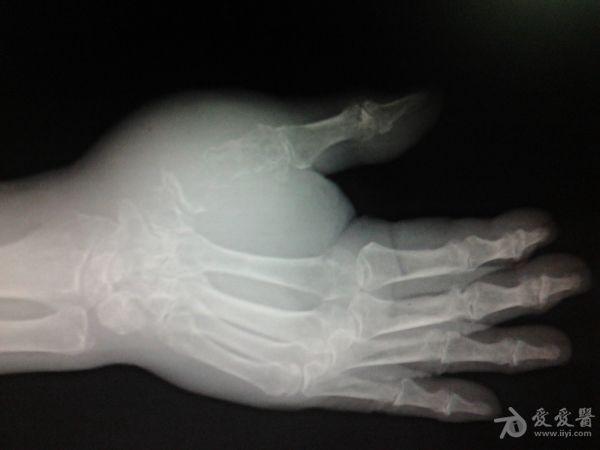

右第一掌骨、大多角骨肿瘤

男性患者,81岁,右手肿痛3个多月。无任何其它症状。体查:右手第一掌骨部肿胀明显,第一指活动受限,余四指活动可,腕关节活动小部分受限,活动时会痛。影像学检查如下。活检示:弥漫性大B细胞淋巴瘤。大家看看需不需要截肢?现在有人主张手术;有人主张不手术,直接化疗。大家有什么看法?

从以上资料看已经影响到腕关节了,还是截吧,不能姑息